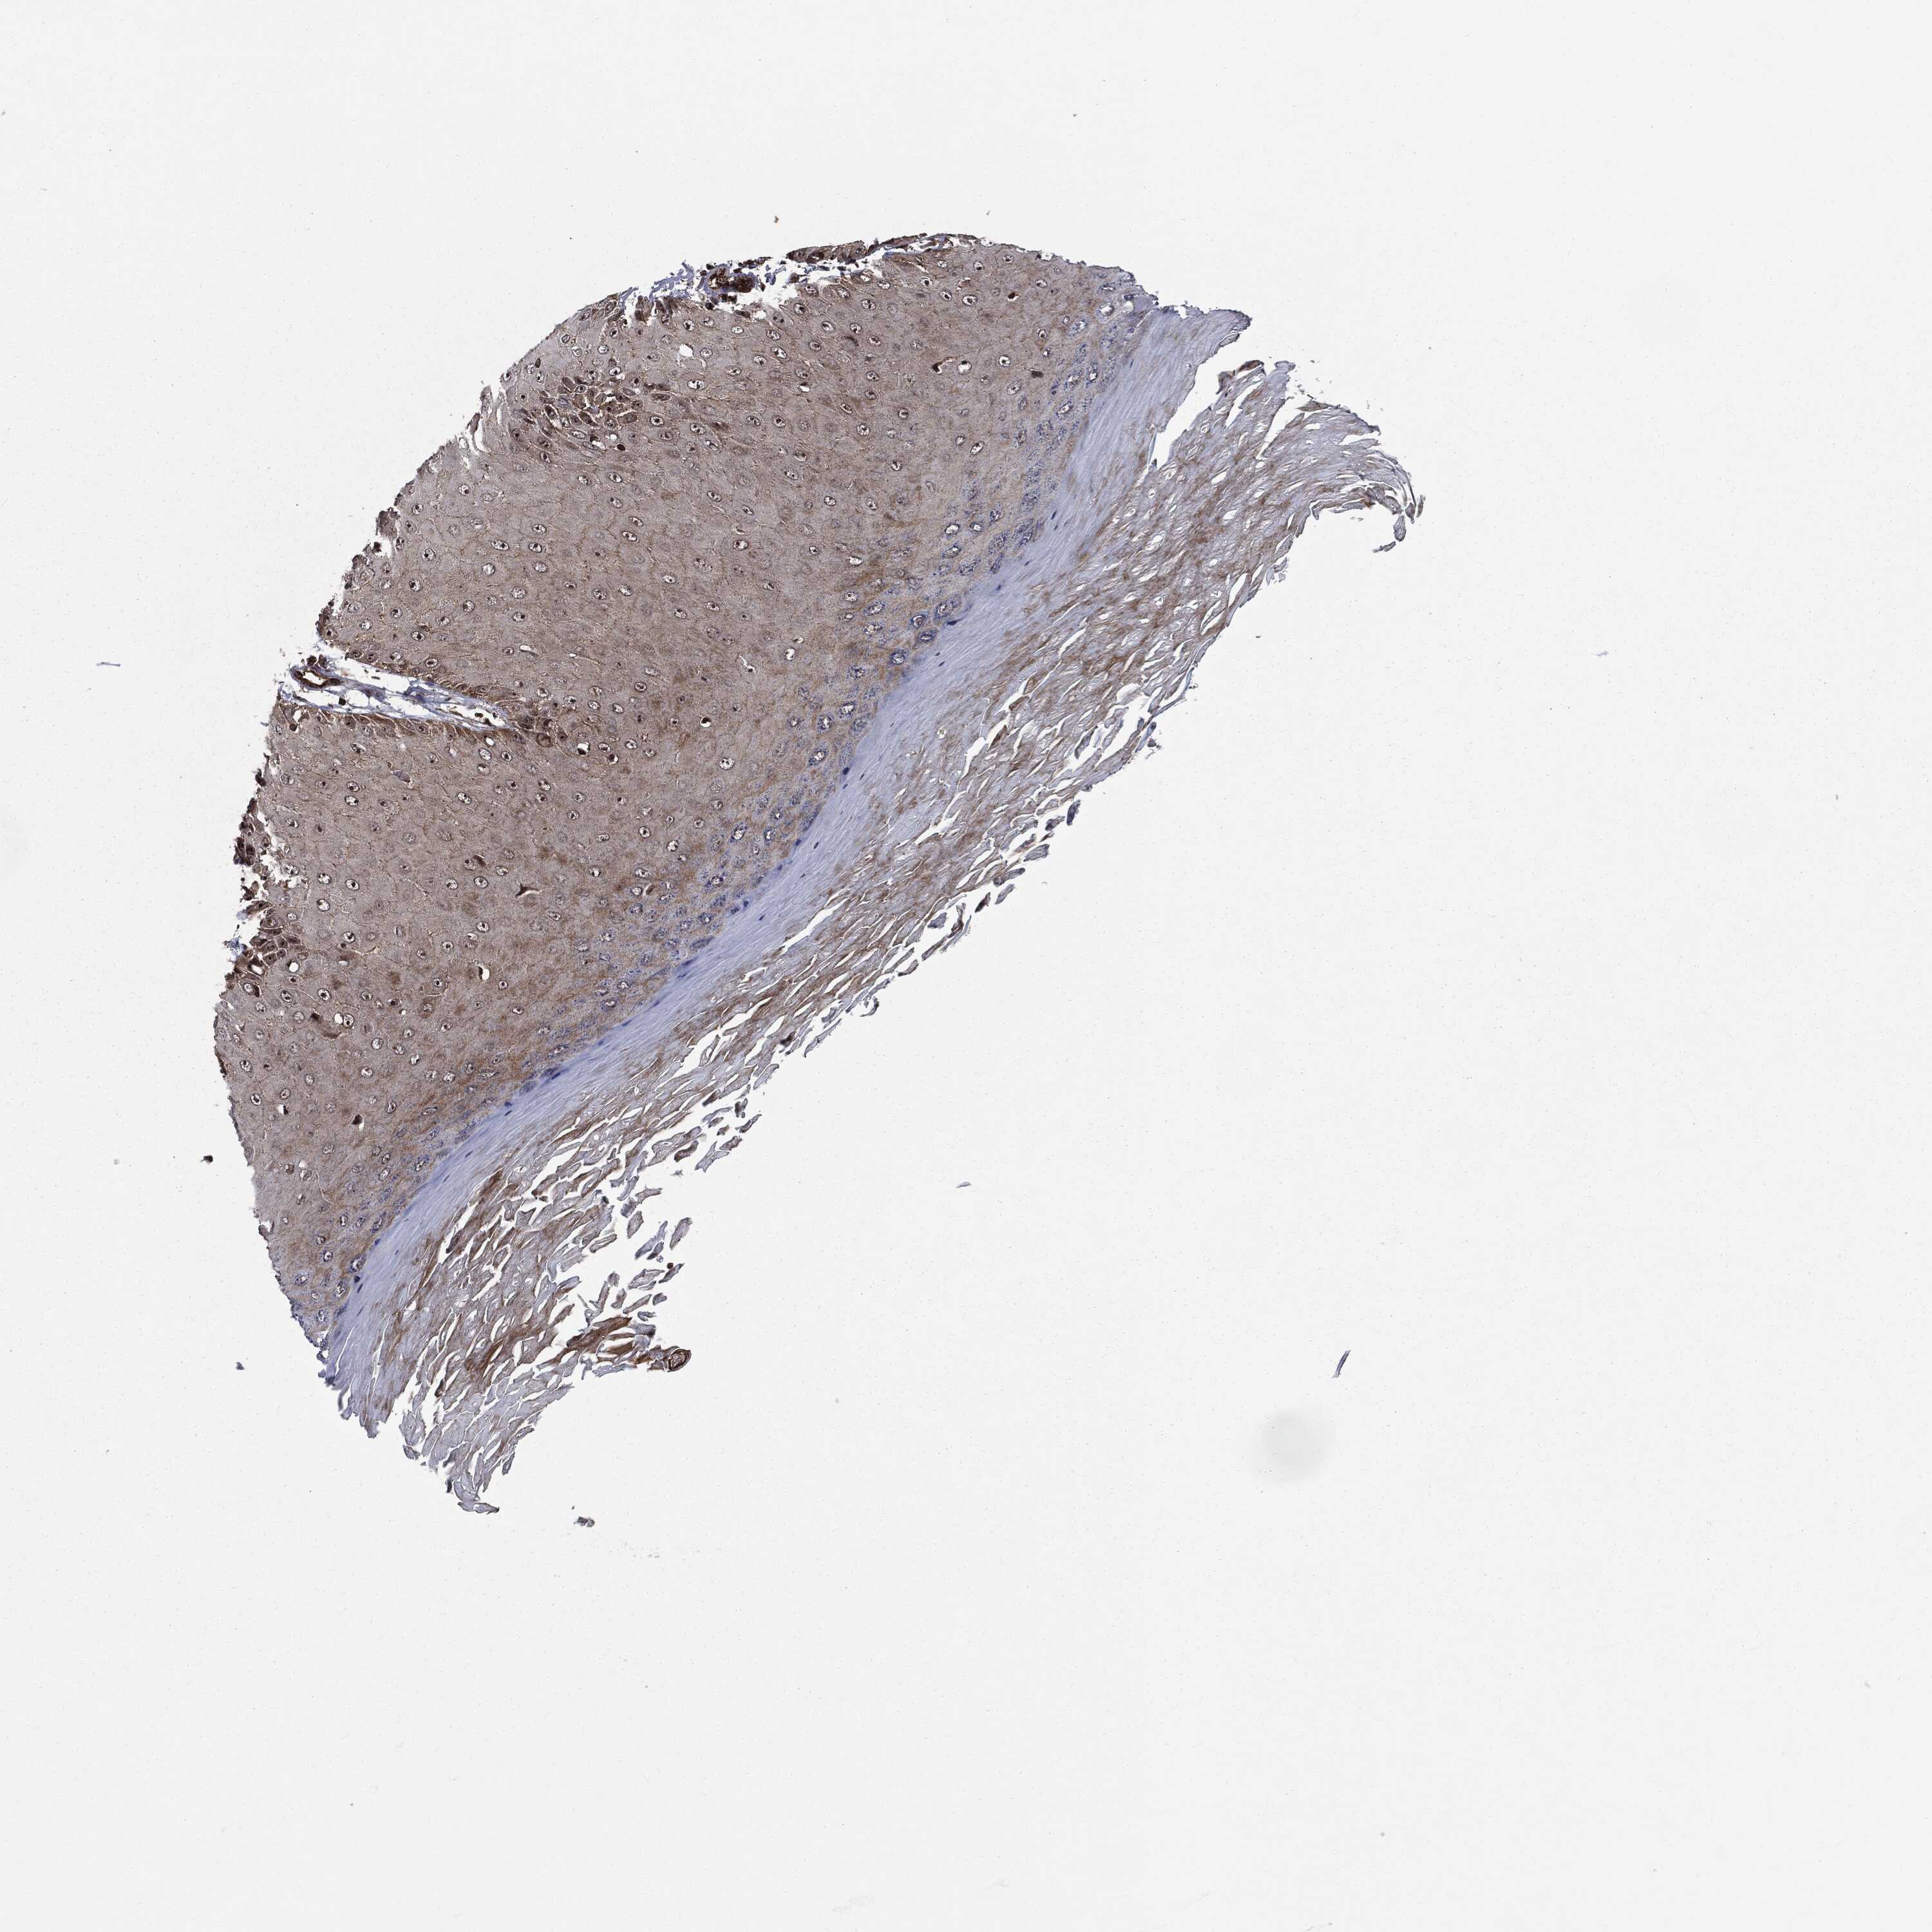

SKIN CANCER - Protein expressioni

A mouse-over function shows sample information and annotation data. Click on an image to view it in a full screen mode. Samples can be filtered based on level of antibody staining by selecting one or several of the following categories: high, medium, low and not detected. The assay and annotation is described here.

Antibody stainingi

Antibody staining in the annotated cell types in the current human tissue is reported as not detected, low, medium, or high, based on conventional immunohistochemistry profiling in selected tissues. This score is based on the combination of the staining intensity and fraction of stained cells.

Each image is clickable and will lead to virtual microscopy that enables deeper exploration of all samples and also displays staining intensity scores, fraction scores and subcellular localization as well as patient and tissue information for each sample.

Antibody HPA041933

Staining

High

Intensity

Strong

Quantity

>75%

Location

Nuclear

Basal cell carcinoma

Squamous cell carcinoma, NOS